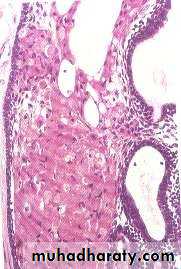

• Histopathology:

• Usually there are many histological• Variants of ameloblastoma.

• 1. Follicular ameloblastoma.

• Islands or trabeculae of epithelial cells

• in a connective tissue stroma

• Ameloblast-like cells" which have " reversed polarity“

• These pattern of growth resembling the early stages of tooth development

• Core of loosely arranged polyhedral or angular cells resembling satellite reticulum

• Variants of ameloblastoma.

• 2. Plexiform ameloblastoma:

• Arranged in a network or anastomosing strands• 3. acanthomatous amploblastoma.

• central core of the neoplastic epithelium shows squamous metaplasia